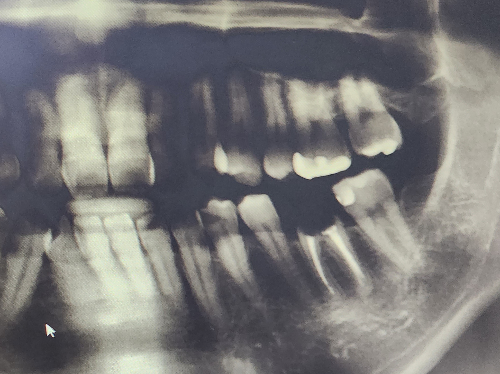

주로 사용하는 어금니 치아가 손을 쓸 수 없을 정도로 심하게 썩어 버려서 임플란트를 하기로 결정했습니다.

치과에서 아직은 잇몸 상태가 좋은 편이라 발치 후 바로 식립 하는 방식으로 진행할 거라고 안내받았는데요.